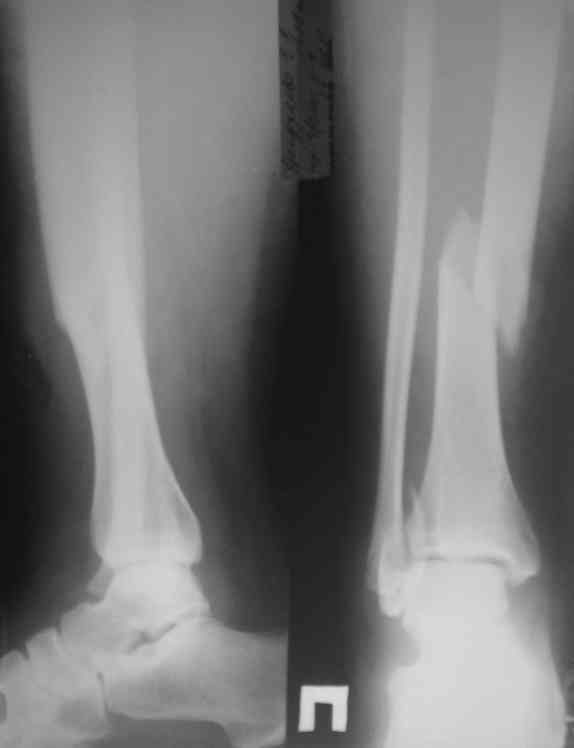

На представленных рентгенограммах укорочения по длинне, т.е. смещеия в таранно-тибиальном суставе - нет. Истинная картина появится поле устрнения смещения по длинне большеберцовой кости.В любом случае нужно предполагать 3-ий вариант.

Все более банально - разрыв межкостной мембраны выден на исходном снимке - внимательней рассмотрите расстояние между берцовыми костями выше и ниже места перелома большеберцовой кости - Вам станет это понятно и без МРТ. А интраоперационно на малоберцовой кости пришлось сопоставлять не дистальный отломок к проксимальному, как это обычно приходится делать при переломе лодыжки, а наоборот - проксимальный отломок к дистальному. т.к. проксимальный отломок малоберцовой кости нестабильной из-за разрыва межкостной мембраны.

С Новым годом! По спирали надо ожидать перелом м\берцовой в с\3 или в в\3. Надо доснять.

Внимательнее рассмотрите рентгенограммы. Перелом малоберцовой имеется в нижней трети. Двойной перелом малоберцовой маловероятен.

Представляю рентгенограмму перелома обеих костей голени, где определяется разрыв дистального межберцового синдесмоза.

Механизм травмы - подвернул ногу. На боковом снимке видно, что латеральная лодыжка поломана на уровне голеностопного сустава. Во время травмы, кроме воздействия крутящего момента на кости голени, происходило еще и стремительное движение тела больного вниз вместе с проксимальным отломком малоберцовой кости (сила земного притяжения), вследствие чего разрывается межкостная мембрана, передняя межберцовая связка (lig.tibiofibulare anterius), рудиментарная поперечная связка. На боковом снимке конец проксимального отломка ( в данном случае место прикрепления передней межберцовой связки) находится на уровне середины таранной кости. Соответсвенно, последняя разорвана. Смещение отломков костей голени по длине - около 2 см.

Соответственно, из составляющих ДМС осталась целой

лишь задняя межберцовая связка. Хирургу, который будет оперировать пациента, рекомендовано наложить шов передней межберцовой связки, и ввести позиционный винт выше ДМС.